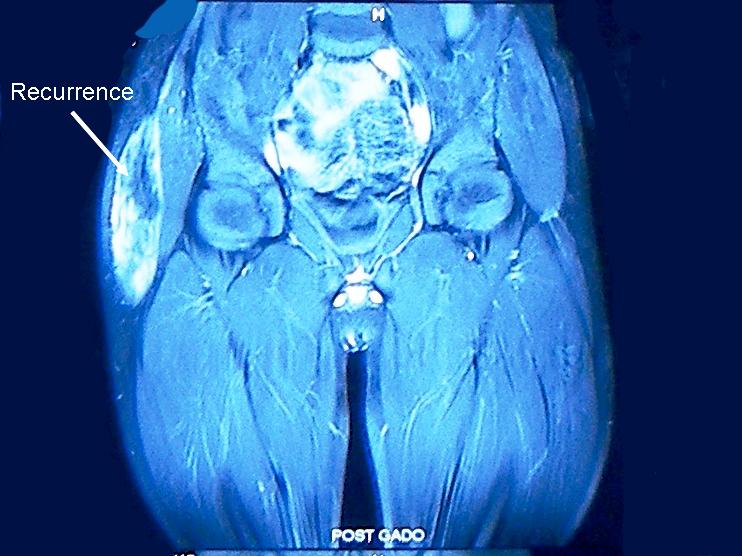

published before [1]. On 1 year follow up, the patient had local recurrence

measuring 8 cm X 5 cm infero-laterally to the

previous scar. MRI of the local region showed a large well defined

heterogeneously enhancing soft tissue mass in subcutaneous layers involving ilio-tabial tract with areas of deep multiple recurrences

(Fig. 1). There was no evidence of metastasis. Local excision was done.

Figure 1: MRI showing large subcutaneous local recurrence

and multiple small deep recurrences.